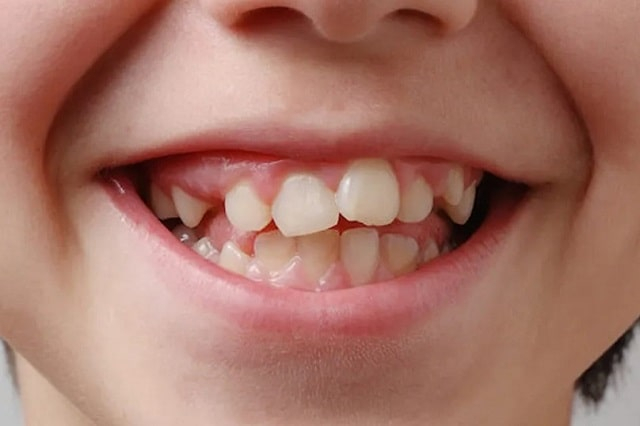

Чаще всего ретинированы именно третьи моляры (зубы мудрости), поскольку для них может просто не хватить места в челюсти. На втором месте — клыки, особенно верхние, которые играют важную роль в формировании прикуса.

Ретенция бывает:

- Полная — зуб полностью скрыт под десной и костной тканью.

- Частичная — зуб частично прорезался, но не до конца.